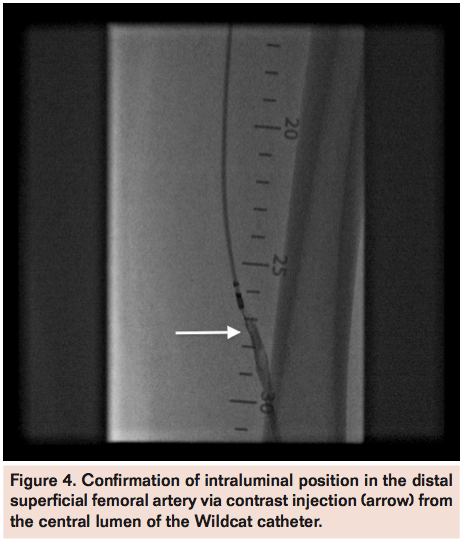

occluded segment and 2 overlapping Supera 5 mm x 120 mm self-expanding stents (IDEV Technologies) were deployed in the left SFA. The final angiogram revealed brisk flow with 3-vessel runoff into the left foot (Figure 5). The patient tolerated the procedure well without complications and was discharged home the following day after observation post-intervention.